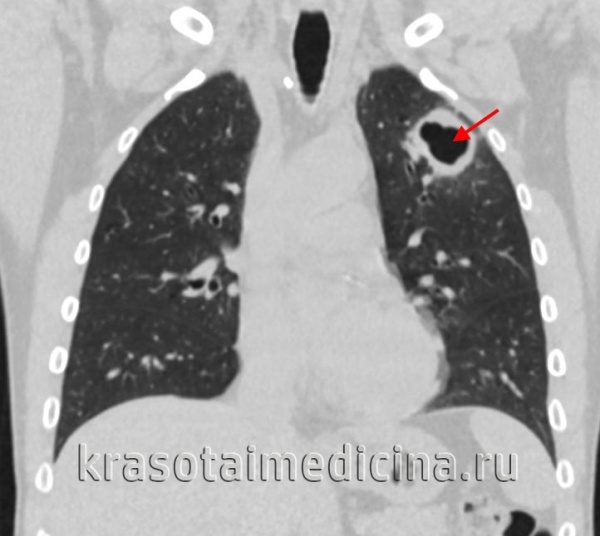

- Кавернозный туберкулез легких. Тяжелая форма туберкулеза, при которой происходит деструкция легочной ткани и образуются большие каверны (полости) в легком. Возникает как осложнение других форм туберкулеза.

- Фиброзно-кавернозный туберкулез легких. Является завершающим этапом кавернозного туберкулеза, когда окончательно формируется полость в легком.

Кавернозный и фиброзно-кавернозный туберкулез легких

Характер течения кавернозного туберкулезного процесса волнообразный. В фазу распада нарастают интоксикационные симптомы, гипертермия, усиливается кашель и увеличивается количество мокроты, возникает кровохарканье. Часто присоединяется туберкулез бронхов и неспецифический бронхит.

Фиброзно-кавернозный туберкулез легких отличается формированием каверн с выраженным фиброзным слоем и фиброзными изменениями легочной ткани вокруг каверны. Протекает длительно, с периодическими обострениями общеинфекционной симптоматики. При частых вспышках развивается дыхательная недостаточность II-III степени.